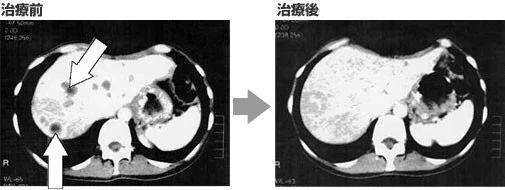

肝脏CT显示有肿瘤,肿瘤标志物AFP高达1966(正常值为10以下)。

过了个把月,肖女士肝转移的肿瘤开始消失,肿瘤标志物也开始下降。

在经过几次回输后,肖女士不仅肿瘤消失了,而且身体情况、精神层面也得到了确切的恢复,能够去旅行,享受人生。